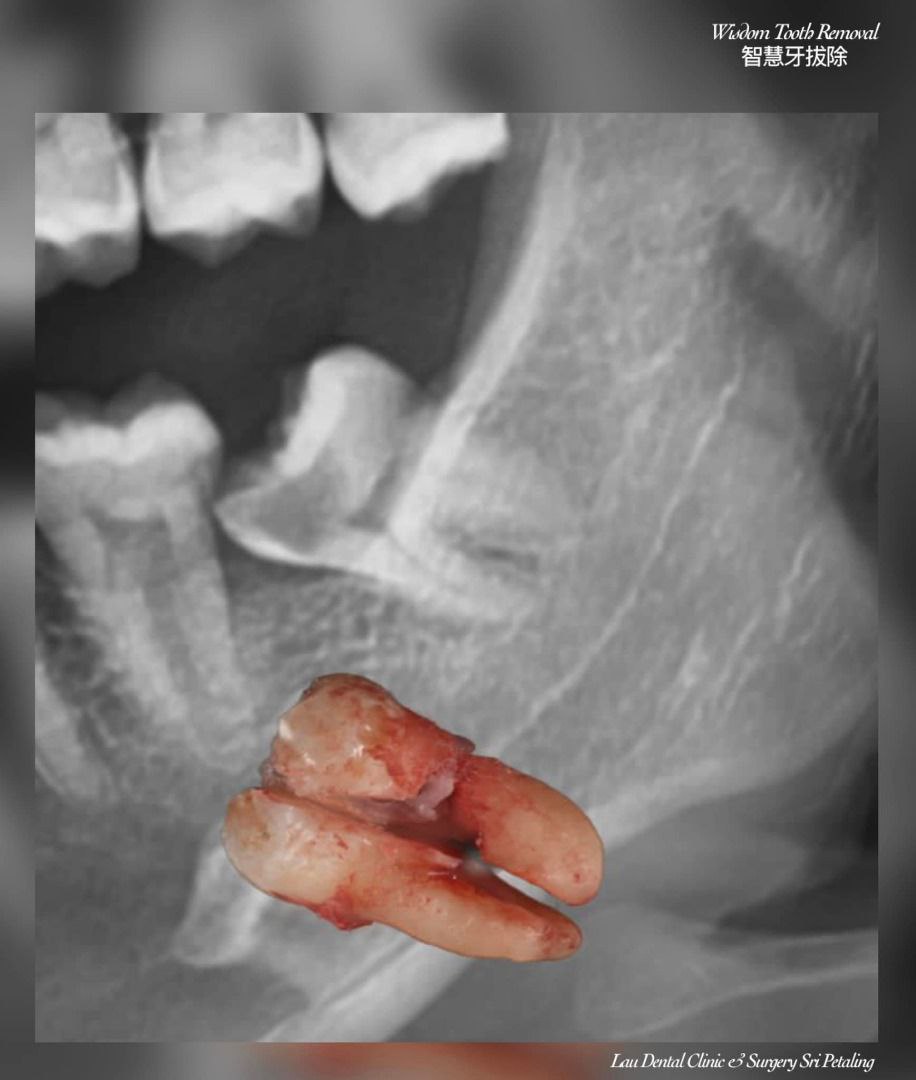

If you've ever had a wisdom tooth that just won't stop aching, or you've been told your tooth is "impacted," chances are you've heard about Minor Oral Surgery (MOS). While the name might sound intimidating, MOS is actually a straightforward and commonly performed dental procedure — and at Lau Dental Clinic & Surgery, we make the experience as smooth and stress-free as possible.

Minor Oral Surgery involves small surgical procedures done inside the mouth, often under local anaesthesia. The most common reason patients need MOS is to remove impacted or partially erupted wisdom teeth. However, it’s also used for removing broken tooth roots, treating dental cysts, or even preparing the mouth for dentures or implants. Unlike major surgery, MOS is minimally invasive, doesn’t require general anaesthesia, and is usually completed in under two hours.

Once you're comfortable and the area is numb, our experienced dentist gently makes a small incision to access the tooth or problem area. Depending on the complexity, the tooth may be removed whole or in smaller sections. The site is then cleaned and stitched if necessary. Most MOS procedures here take only about 1 to 1.5 hours, and patients are often surprised by how quick and painless it feels.